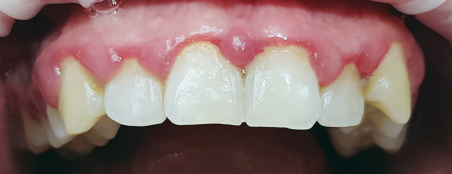

Наши работы

Перед началом лечения делаются цифровые фотоснимки полости рта. Эти съемки регулярно повторяются, чтобы фиксировать изменения в положении зубов. Еще один способ оценить масштаб проблемы – изготовить гипсовые модели челюстей, чтобы пациент мог убедиться в изменении положения зубов и общей запущенности болезни. Кроме того, на такой модели врачу удобнее проводить все необходимые измерения.